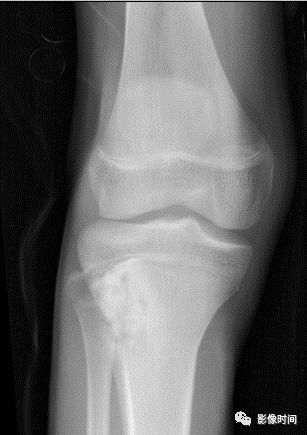

(一)地图样破坏  地图样破坏是指肿瘤组织在一个局部呈团块状生长造成界限清楚的骨质破坏(图 1、图 2、图 3、图 4)。

病灶可位于骨的中心或一侧部位,呈圆形、卵圆形密度减低区,与正常骨质分界清晰,边缘可有或无硬化带围绕,骨的形态无变化,病灶内可完全透亮或可见粗细不均、大小不等的残留骨嵴,内缘可光滑或呈分叶状压迹。

地图样破坏见于大多数良性肿瘤和肿瘤样病变如单纯性骨囊肿、骨纤维结构不良、血管瘤等、也可见于部分恶性骨肿瘤如骨转移瘤、骨髓瘤等。

图 1  地图样破坏:单纯性骨囊肿